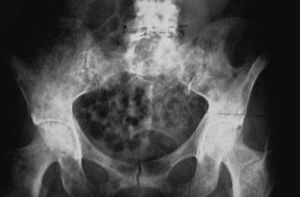

糖尿病性骨質溶解是糖尿病的一種特異性表現。其特徵為骨質疏鬆和遠端跖骨及近端趾骨程度不一的骨質吸收。疼痛程度各異。發病機理不明。本症在糖尿病病程的各個階段均可出現。需要排除的疾病主要是感染性骨髓炎。治療以保守療法為主。症狀可以白行緩解其至完全消失。